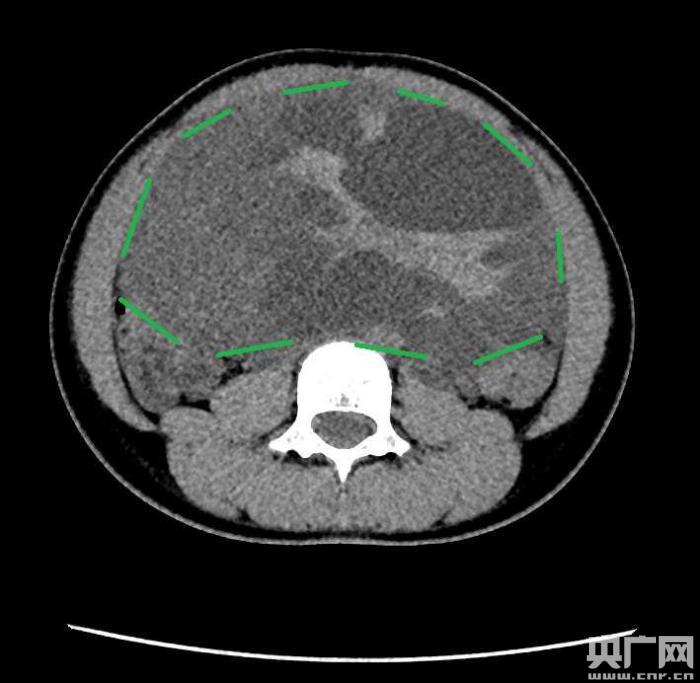

入院后,普外一科肖東主任向家長(zhǎng)詢問了病史,仔細(xì)進(jìn)行了體格檢查,并完善腹部CT。CT結(jié)果提示,孩子的大部分腹腔、盆腔被一個(gè)巨大的腫瘤占據(jù),腸道、血管和腎盂都受到了不同程度的壓迫。從CT上看,腫瘤很可能起源于左側(cè)的卵巢。

手術(shù)中發(fā)現(xiàn),小琪腹中的腫瘤體積巨大,大小約為25×20×15厘米,表面光滑,來源于左側(cè)卵巢。醫(yī)生們首先將其與周圍的組織小心剝離,然后將這個(gè)占據(jù)孩子腹腔、盆腔大部分的巨大包塊完整切除,切除腫瘤后還重建了左側(cè)卵巢。剖開瘤體,發(fā)現(xiàn)瘤體為囊性及實(shí)性混合組成,瘤體內(nèi)部充盈著粘液狀的液體,重量達(dá)到了3000克。術(shù)后小琪病情穩(wěn)定,測(cè)量腹圍從術(shù)前的72厘米減小到了62厘米。